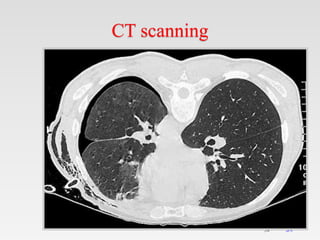

CT scanning

It is recommended in difficult cases such

as patients in whom the lungs are

obscured by overlying surgical

emphysema

To differentiate a pneumothorax from

suspected bulla in complex cystic lung

disease

CT can diagnose easily

pneumothroax